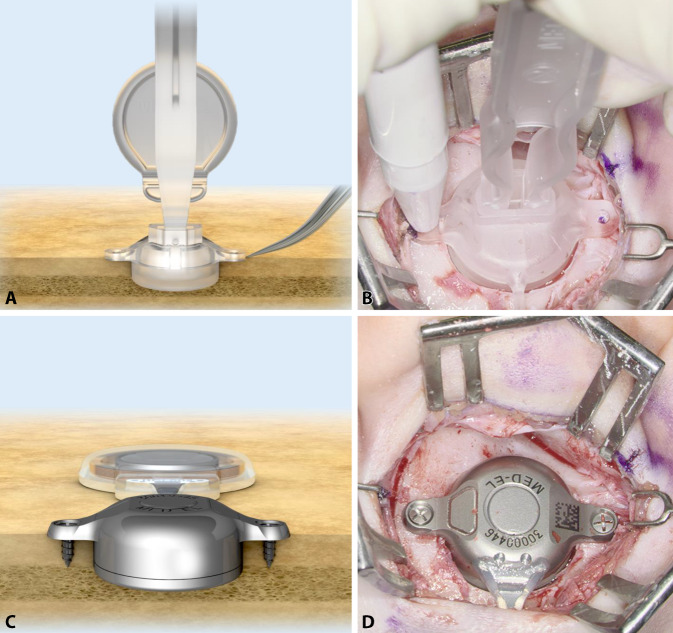

The implant can be bent in the transition zone, ±90° in the horizontal plane and −30° in the vertical plane (Fig. 5). While bending, the implant should be held with the thumbs and index fingers of both hands, one at the positioning aid and one at the BC-FMT (Figs. 1 and 5). The receiver coil and the attachment magnet are placed in a subperiosteal pocket, directly on the skull. The fixation wings with anchor holes should lay flat on the bone (Fig. 6A, B). When pressing the BC-FMT down with a finger, it should not wiggle or wobble. The BC-FMT is then fixed with self-drilling cortical screws (Fig. 6C, D).

Fig. 6.

Fixing the bone conduction-floating mass transducer (BC-FMT) to the bone. A, B The fixation wings with anchor holes should lay flat on the bone. When pressing the BC-FMT down with a finger, it should not wiggle or wobble. C, D The BC-FMT is fixed with self-drilling cortical screws; this procedure is simpler in this model (BCI 602) than in the previous model (BCI 601). (A, C: MED-EL, Innsbruck, Austria, with permission)